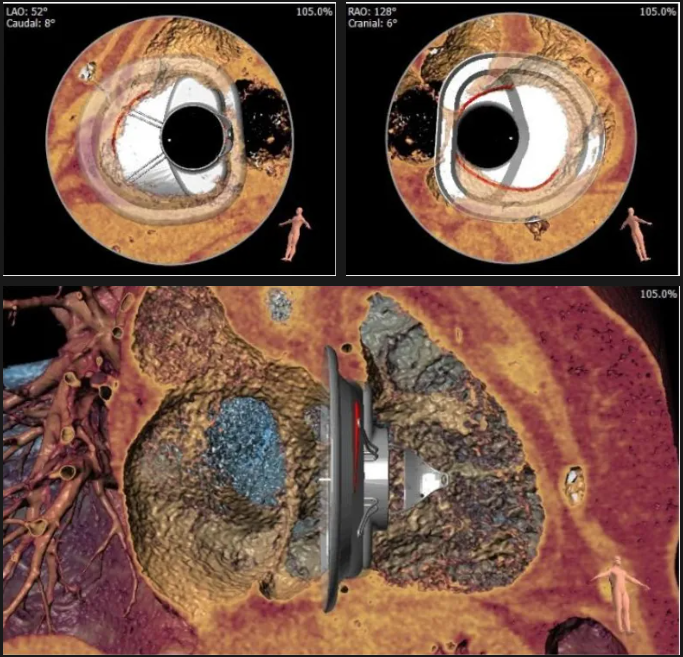

術前心臟CT評估

三尖瓣環平均周長徑54.3mm,最大直徑57mm

心房側周長平均徑(封堵高度)74.0mm

三尖瓣環切線位夾角 103°

夾持件位置確認

室間隔位置確認

術中經食道超聲輔助下可見LuX-Valve Plus夾持件抓捕瓣葉狀態良好,夾持件在位,室間隔錨定位置良好,假體瓣膜整體錨定狀態穩固。

術后即刻經食道超聲可見,三尖瓣假體瓣膜位置合適,牛心包瓣葉運動狀態良好,開閉正常,瓣周及瓣葉對合緣處未見明顯返流,心電圖及心包狀態較術前無明顯變化。